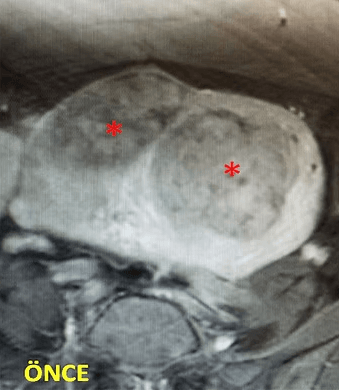

32 yaşında, adet kanamalarında artma ve kansızlık şikayetleri mevcut. Emar’da 2 adet intramural miyom (*) izleniyor. Miyomektomi önerilmiş, ancak gerekirse rahimin alınabileceği söylenmiş. Embolizasyondan sonra miyomların öldüğü ve küçüldüğü izleniyor. İşlemden 2 ay sonra hastanın adetleri normalleşmiştir.